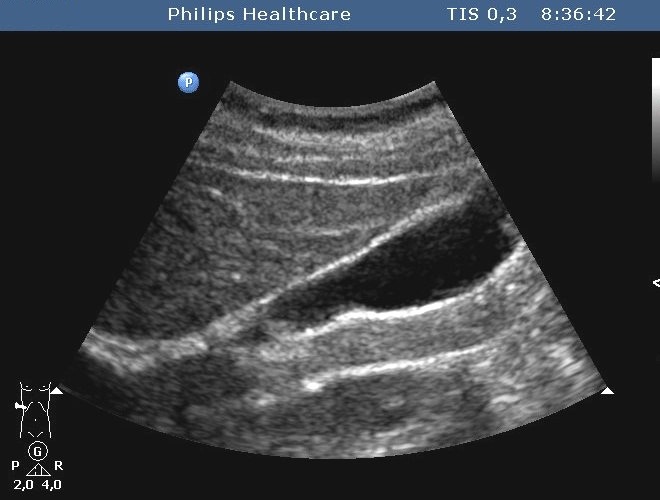

The spleen cysts occur less frequently then the liver cysts, their morphological appearence is similar to that of the liver cysts (homogeneous, cystic content, sharp contour, thin wall, sometimes some thin septa). Most of them is detected only accidentally. It has a therapeutic consequence if its size increases resulting symptoms for the patient by the compression of the sorrounding tissues (Figure 47, 48).

Figure 48: Spleen cyst, contrast enhanced CT